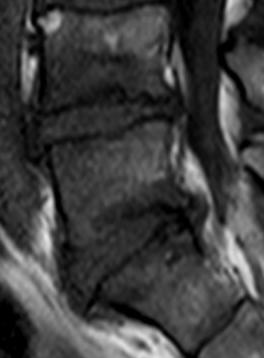

Discopathies L4-L5 et L5-S1 MODIC 1